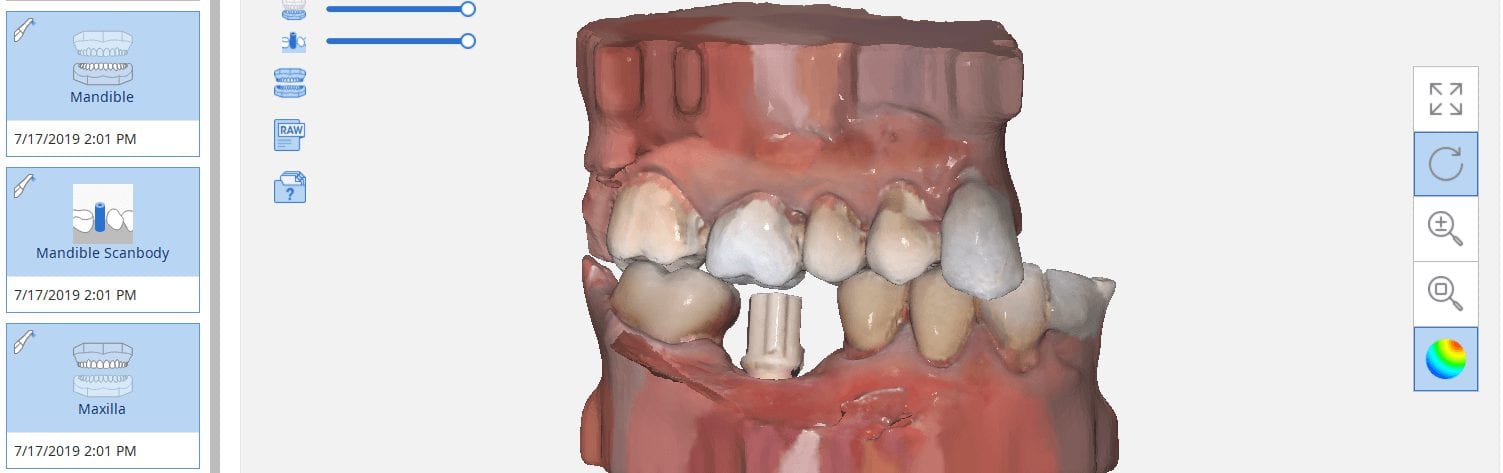

July 18, 2019There are multiple ways one can capture the bite for a patient. In this clinical case, we focus on the easiest way to capture two bites (one in maximum intercuspation […]